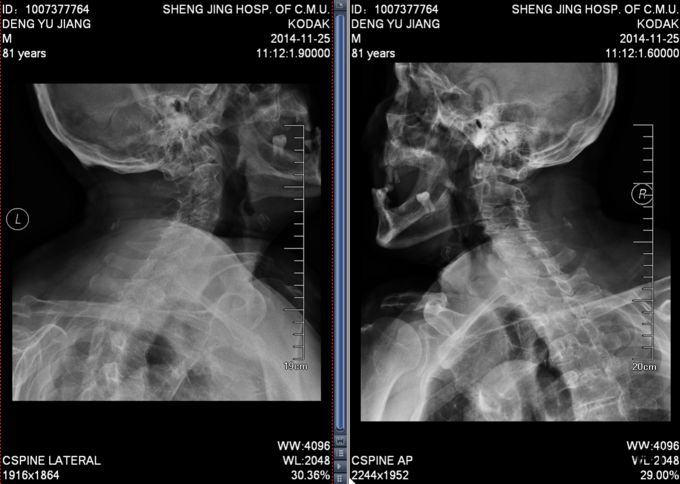

患者男,81岁,自述于1个月前出现双上肢感觉减退,发胀,以左侧为重,后来加重,左侧握力减退,于201医院就诊,行颈椎MR检查,提示为颈3-4、4-5间盘突出,为求进一步治疗就诊于我院,患者病来饮食、睡眠佳。大小便正常,体重无明显变化。

颈椎生理弯曲消失,活动度正常。双上肢感觉减退。双手握力(R5级,L4级),伸肘肌力(R5级,L5级),屈肘肌力(R5级,L5级),Hoffman(R-,L+)桡动脉搏动有力,末梢血运良。

诊断:颈椎病,颈椎间突出,高血压病 患者入院后完善相关检查,请相关科室及麻醉科会诊,医院医务部审批后,查无其他手术禁忌症,于全麻下行颈椎后路单开门椎管扩大减压侧块螺钉内固定术。术后给予患肢雾化祛痰,抗炎,消肿,营养神经,接骨等对症治疗。术后患者在颈领的保护下可下地行走,术后14天拆线后予以出院,